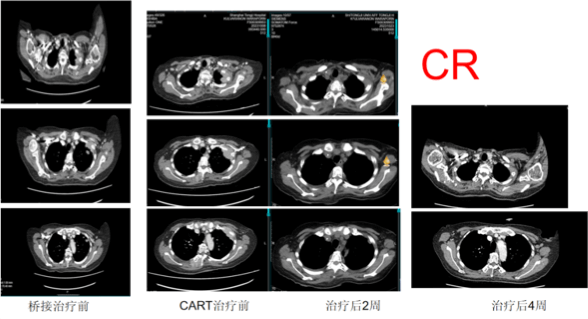

Tumors Completely Disappeared in 22 Days! CAR-T Treatment Sets Survival Miracle

What shocked everyone was that the examination results 22 days after CAR-T treatment showed that Ms. M had achieved hematologic CR, meaning that no cancer cells were detected in her blood. Her pain and anemia were also reversed. It was simply a miracle!

Ms. M's daughter exclaimed excitedly: "When we first arrived in China, my mother had lost 10 kilograms due to illness. She couldn't move because of the pain and couldn't eat anything. Even though our family tried our best to prepare food, she couldn't swallow anything. Even with morphine, her pain couldn't be alleviated. These painful memories are vividly recalled as if they were just yesterday. My family and I simply couldn't believe that a miracle had truly happened. After receiving CAR-T treatment, my mother began to improve rapidly. Just one week later, her pain was almost gone, and she could stand for a long time and even do some things she liked."